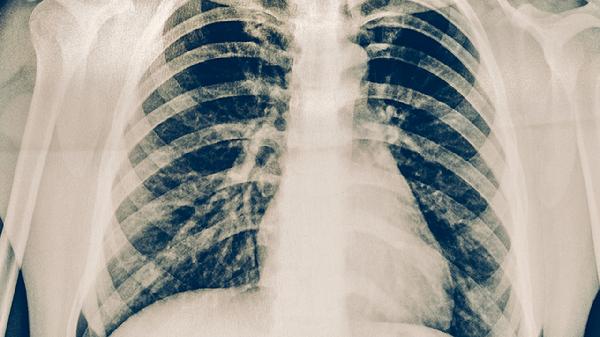

对于80多岁的老人,如果出现肋骨骨折,可以通过镇痛治疗、呼吸训练、体位调整、预防并发症和营养支持等方法进行处理。肋骨骨折...

胸肋骨骨折的患者在饮食和药物方面可以适当选择一些有助于骨骼恢复的食物和药品。比如,可以多吃一些高钙、高蛋白、富含维生素D...